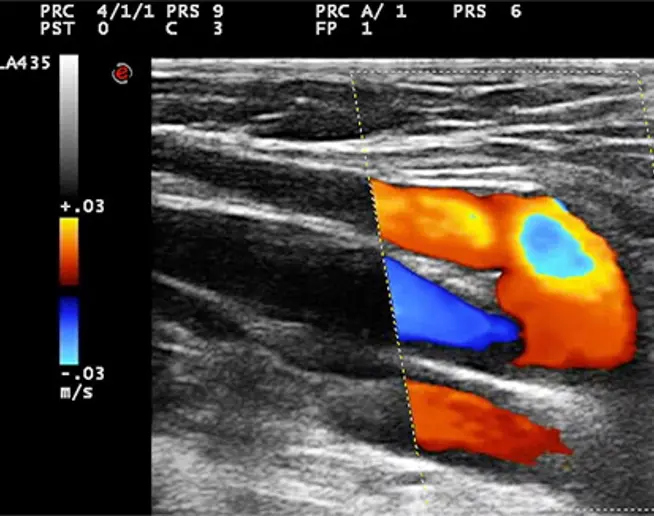

Procedure mini-invasive in anestesia locale, previo marcaggio  B-mode dei siti di interesse chirurgico definiti nella cartografia emodinamica.

Cartografia e strategia personalizzate in base al tipo di shunt in ogni singolo paziente.